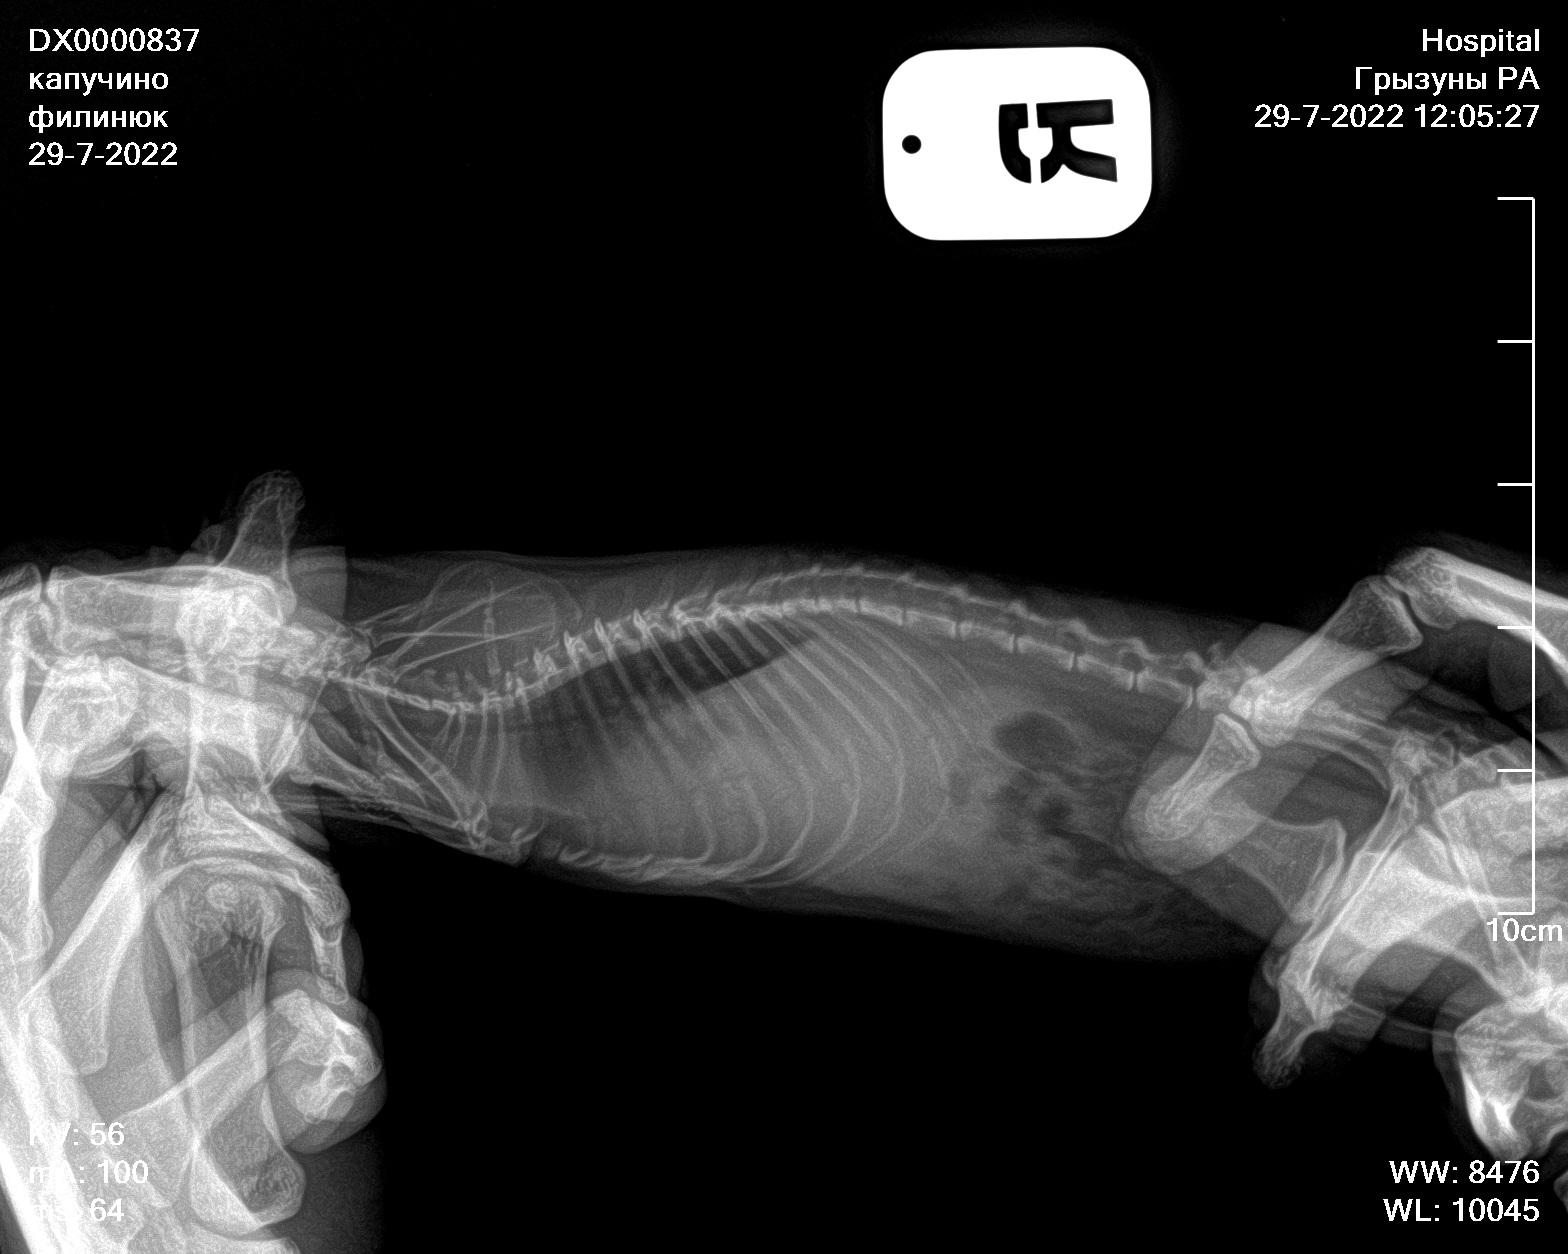

Сделали сегодня рентген новый, посоветовали попробовать продавать 5/5 асд-2 в течении 1-2 месяцев, посмотреть результат

По рентгену надо консультироваться на других форумах или вконтакте, где раньше консультировались, тут я никак не помогу, увы.